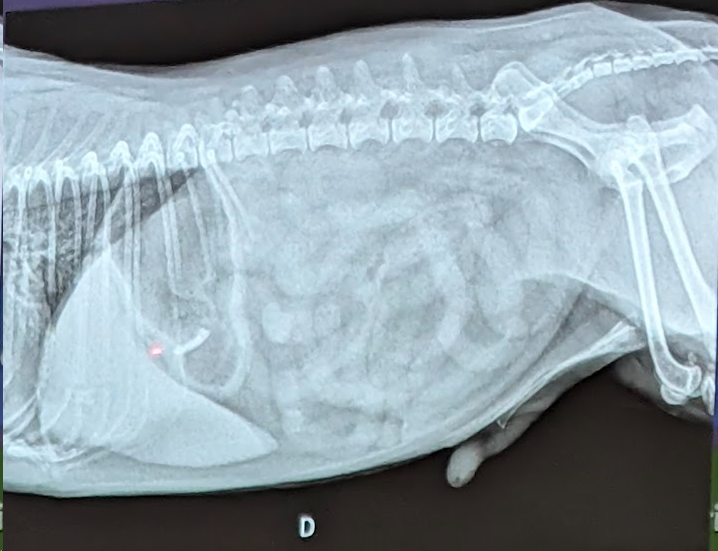

1) Una respuesta correcta

- Patron Intersticial (Difusa, no estructurado, se ve la vena cava y aun hay negros, por eso no es alveolar) IMPORTANTE Patrones bronquiales no suelen entrar porque se ven mal de los donuts